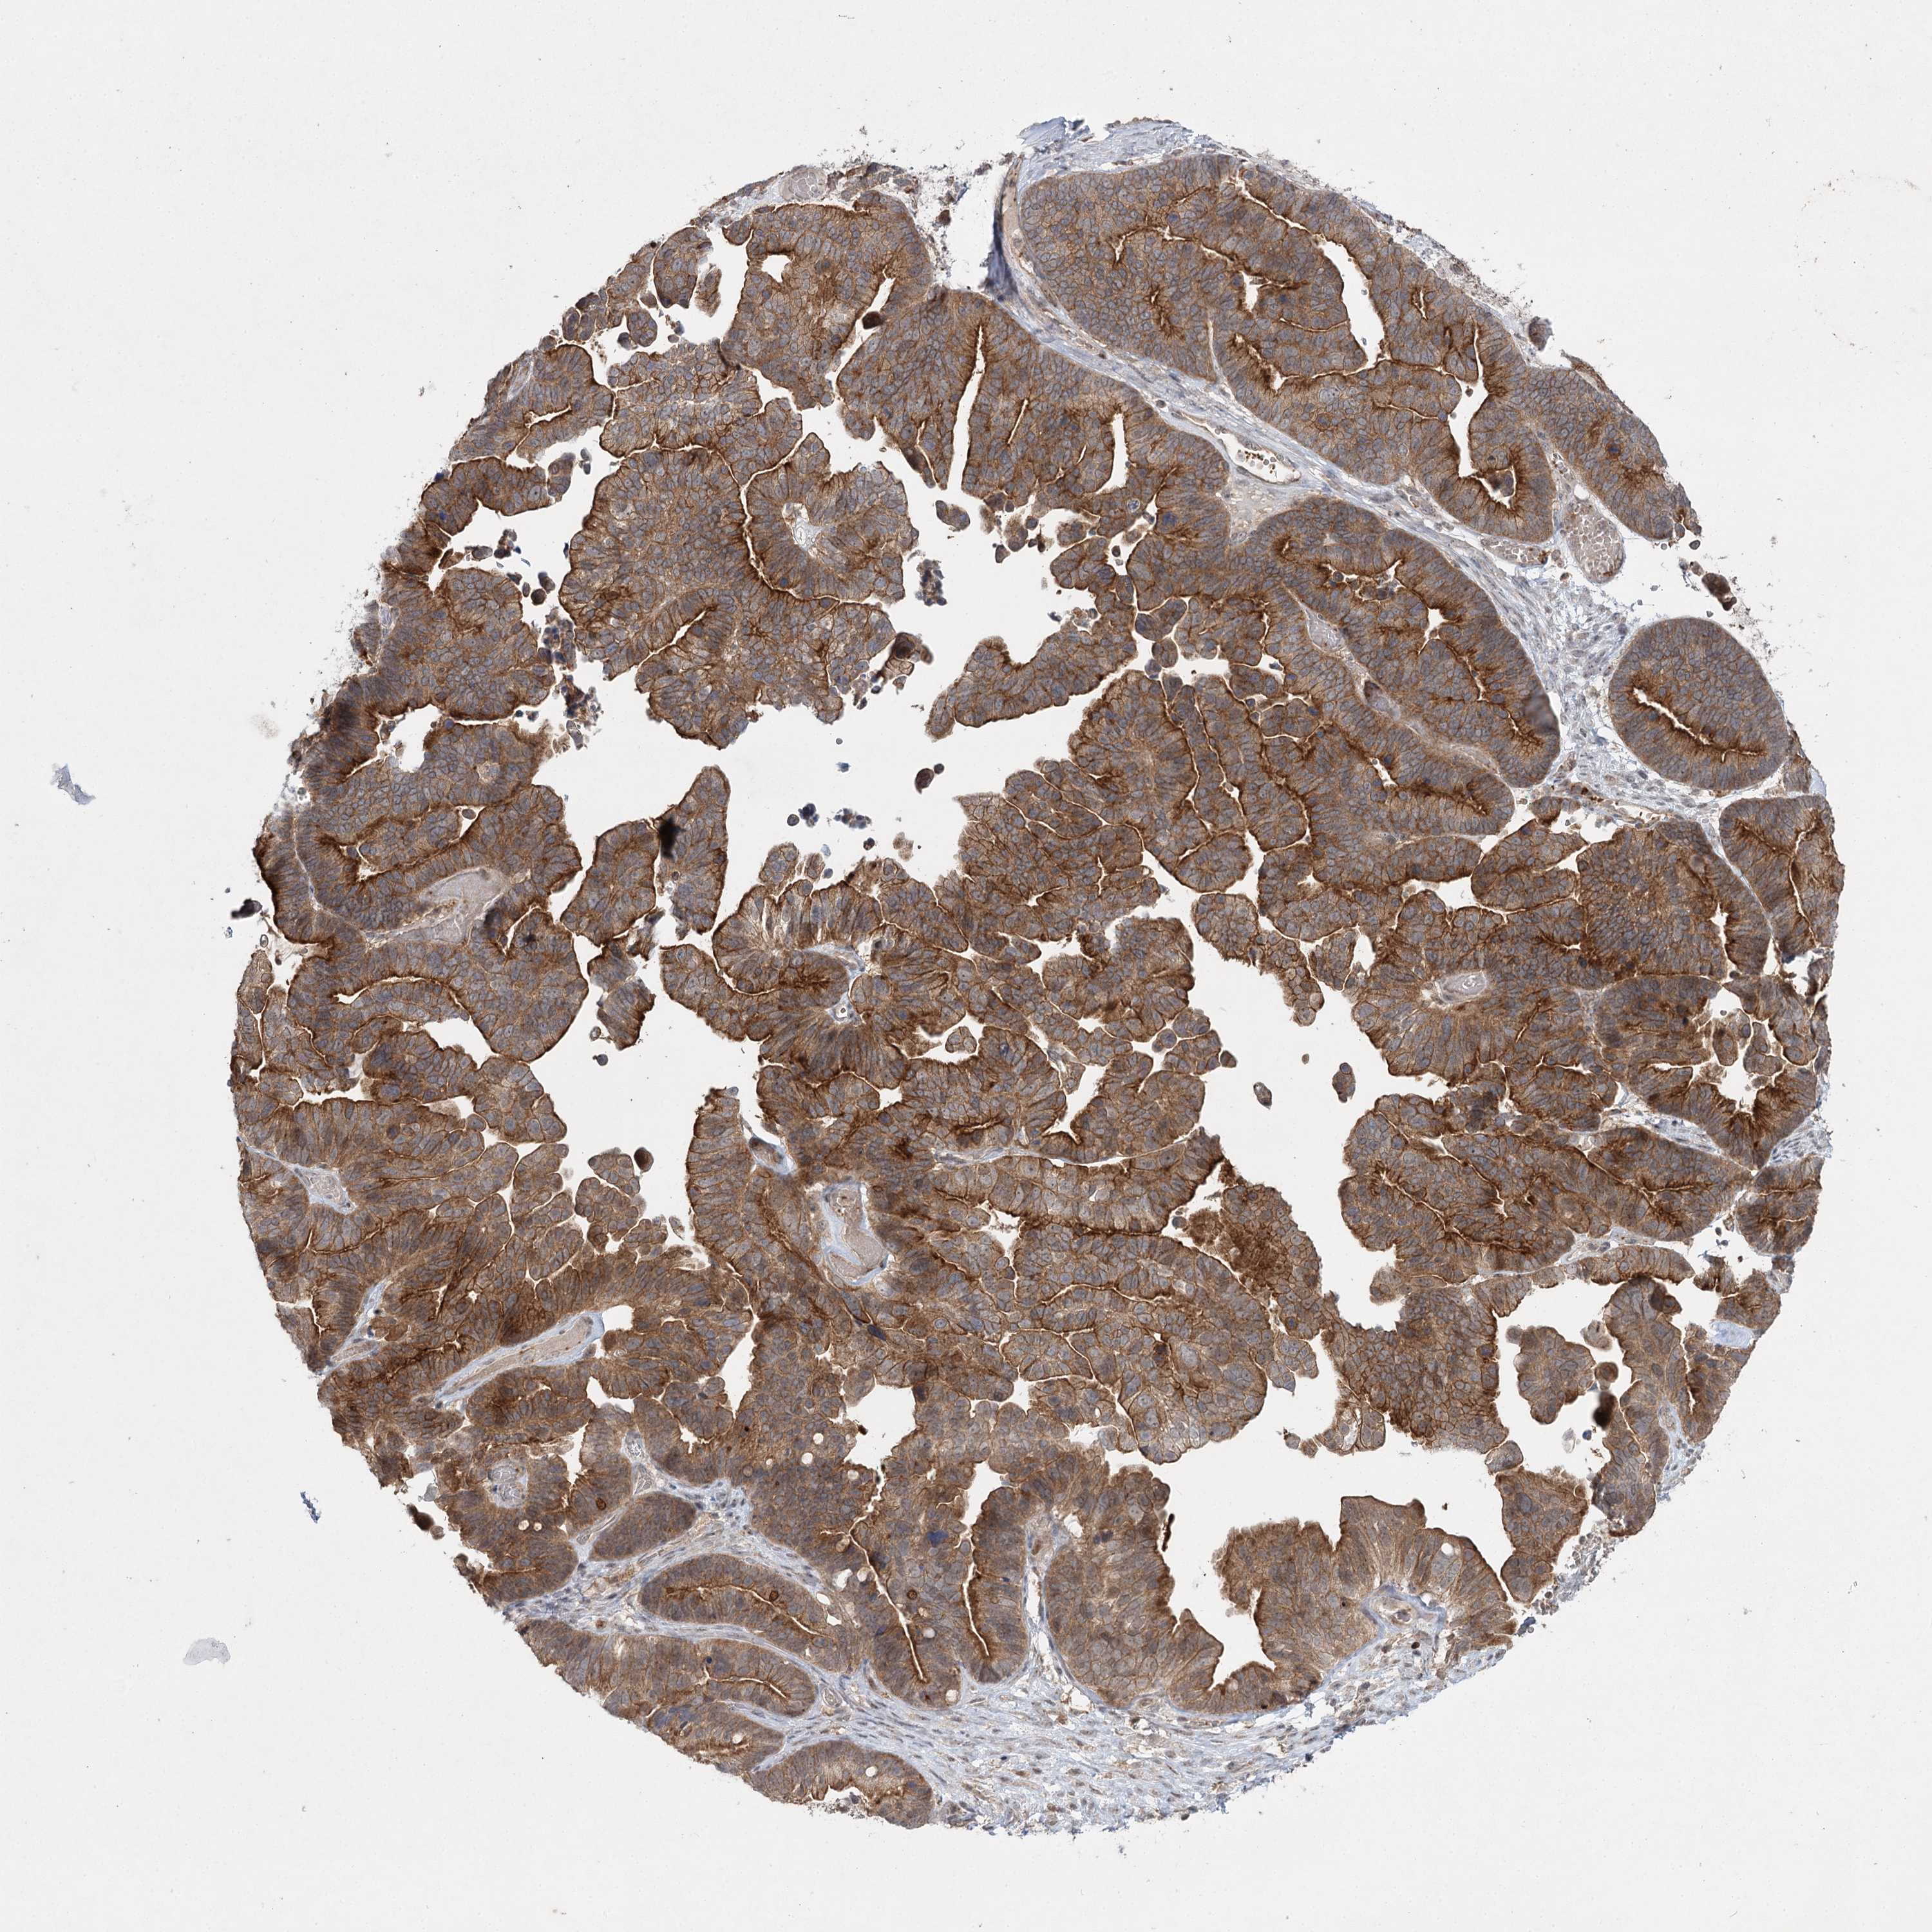

OVARIAN CANCER - Protein expressioni

A mouse-over function shows sample information and annotation data. Click on an image to view it in a full screen mode. Samples can be filtered based on level of antibody staining by selecting one or several of the following categories: high, medium, low and not detected. The assay and annotation is described here.

Note that samples used for immunohistochemistry by the Human Protein Atlas do not correspond to samples in the TCGA dataset.

Antibody stainingi

Antibody staining in the annotated cell types in the current human tissue is reported as not detected, low, medium, or high, based on conventional immunohistochemistry profiling in selected tissues. This score is based on the combination of the staining intensity and fraction of stained cells.

Each image is clickable and will lead to virtual microscopy that enables deeper exploration of all samples and also displays staining intensity scores, fraction scores and subcellular localization as well as patient and tissue information for each sample.

Antibody HPA038084

Staining

High

Medium

Low

Not detected

Intensity

Strong

Moderate

Weak

Negative

Quantity

>75%

75%-25%

<25%

None

Location

Nuclear

Cytoplasmic/membranous

Cytoplasmic/membranous,nuclear

Cystadenocarcinoma, serous, NOS